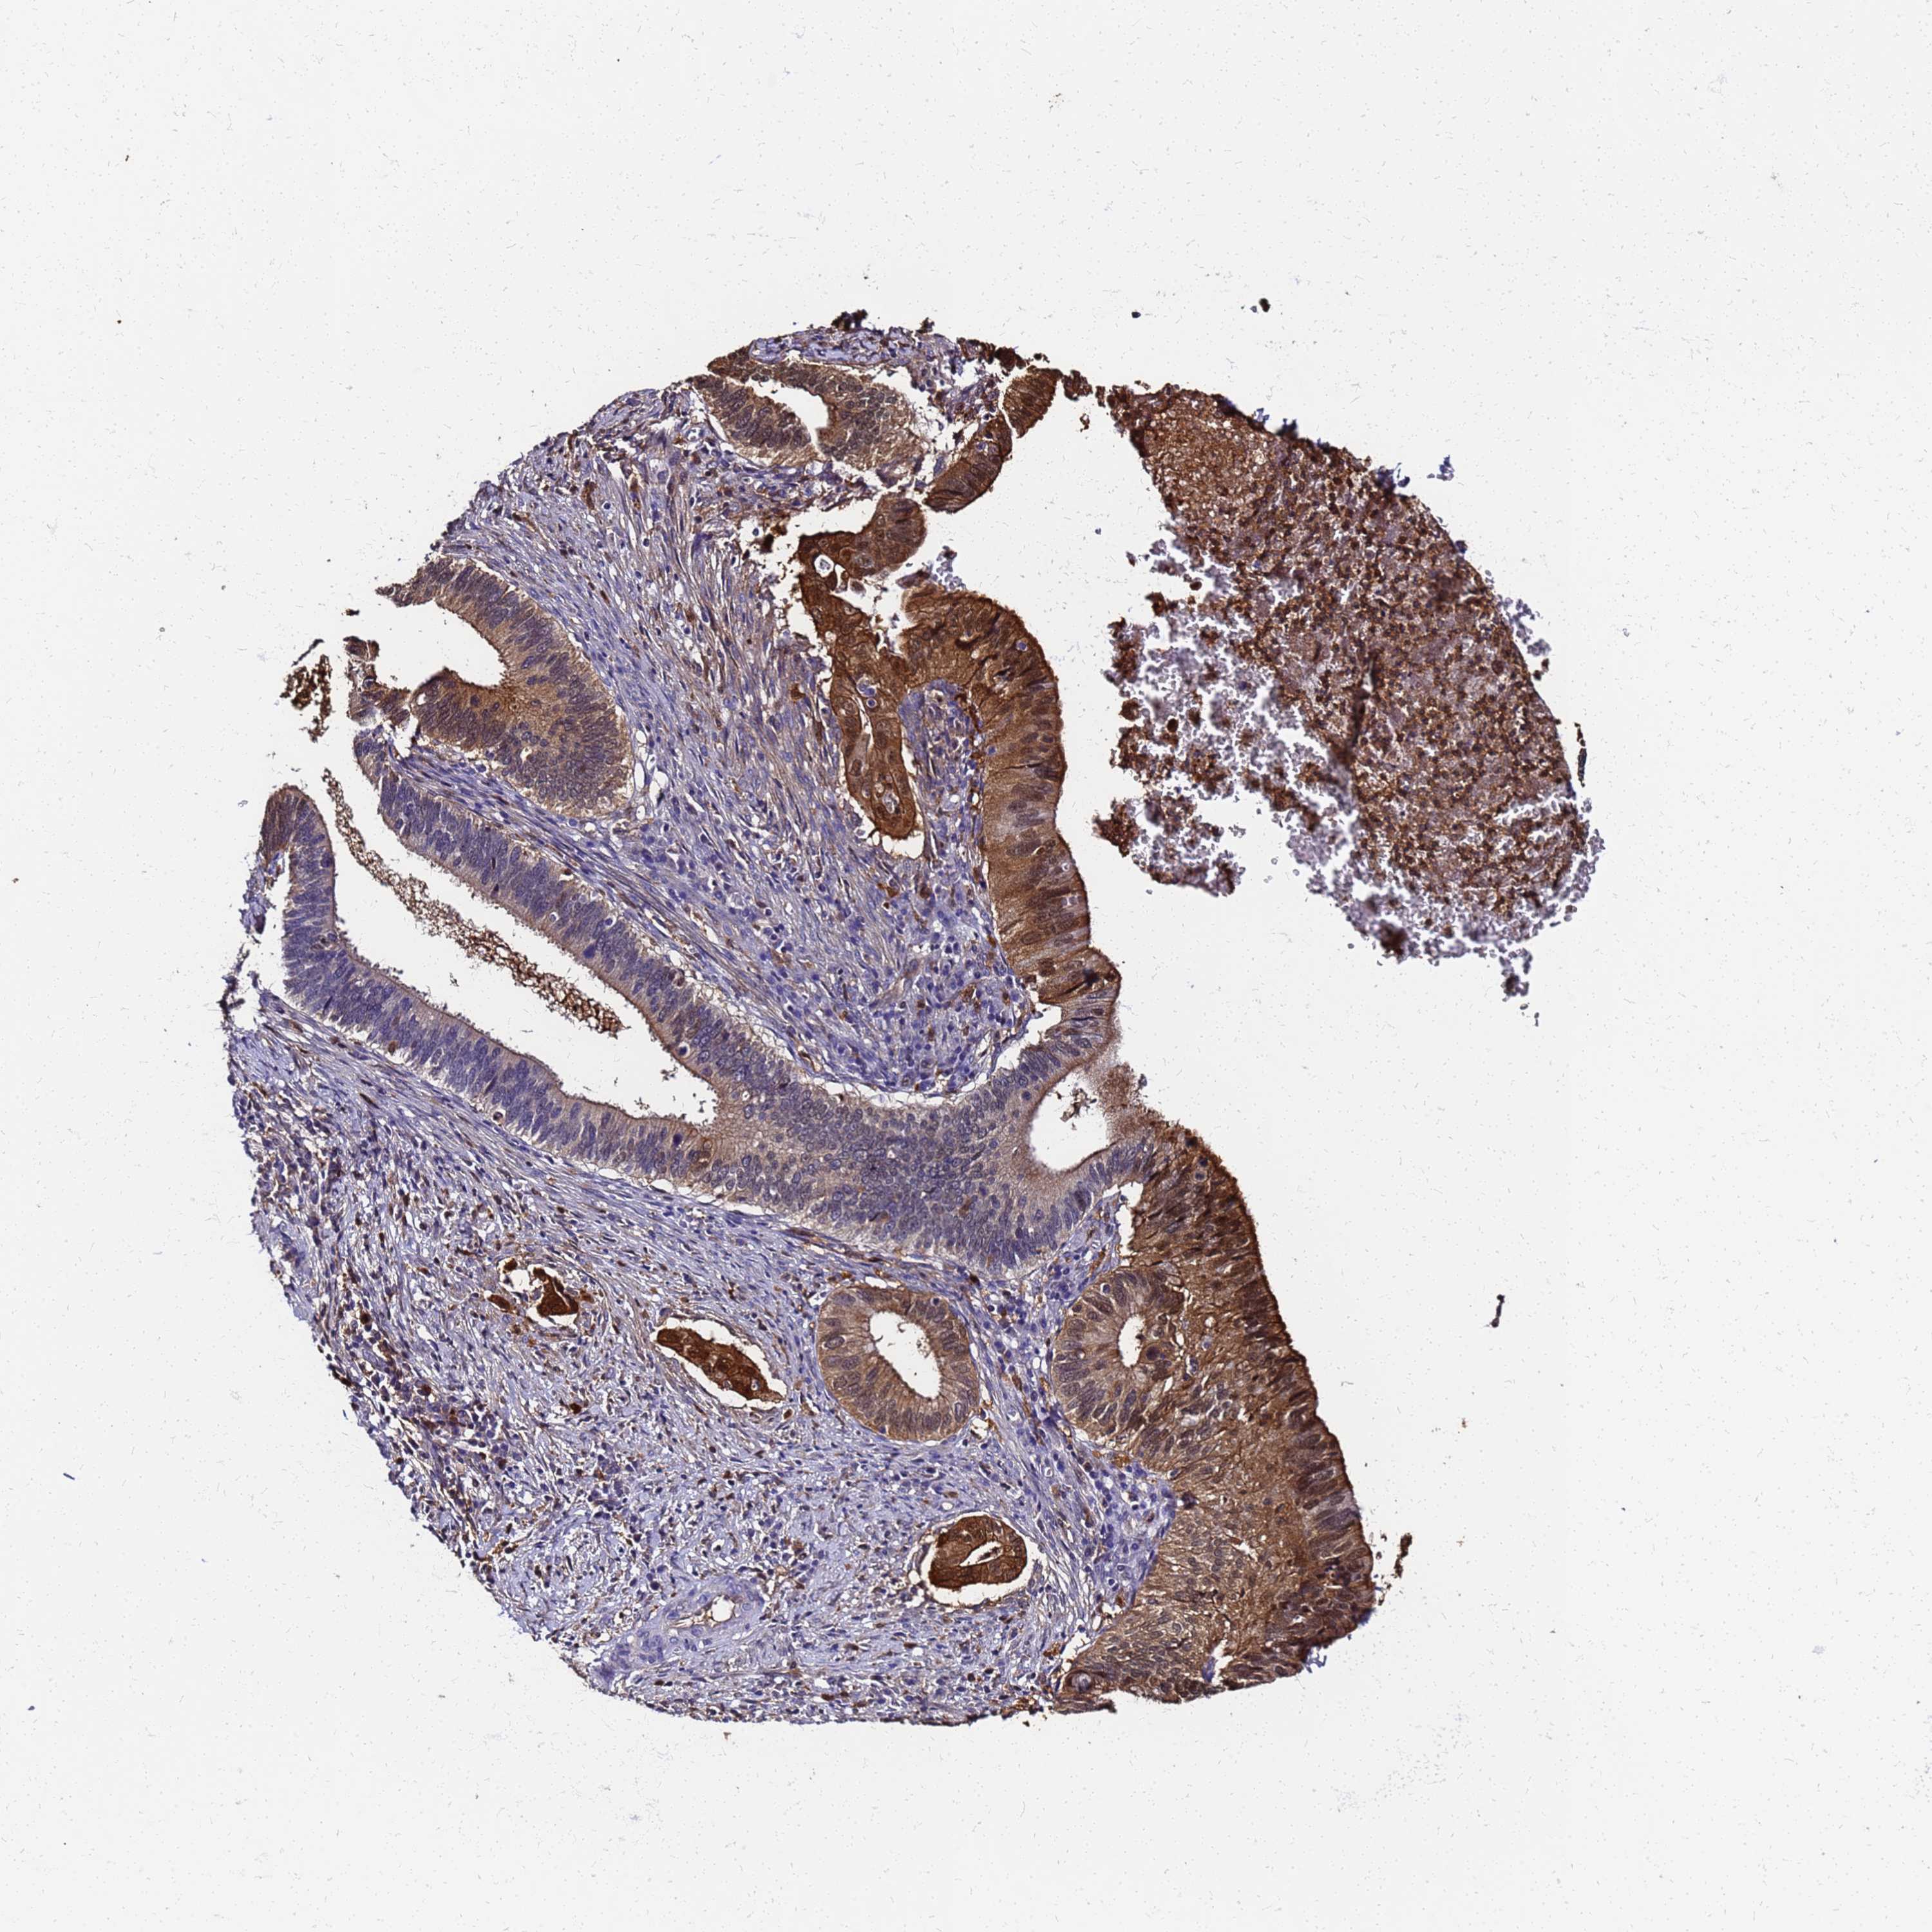

CERVICAL CANCER - Protein expressioni

A mouse-over function shows sample information and annotation data. Click on an image to view it in a full screen mode. Samples can be filtered based on level of antibody staining by selecting one or several of the following categories: high, medium, low and not detected. The assay and annotation is described here.

Note that samples used for immunohistochemistry by the Human Protein Atlas do not correspond to samples in the TCGA dataset.

Antibody stainingi

Antibody staining in the annotated cell types in the current human tissue is reported as not detected, low, medium, or high, based on conventional immunohistochemistry profiling in selected tissues. This score is based on the combination of the staining intensity and fraction of stained cells.

Each image is clickable and will lead to virtual microscopy that enables deeper exploration of all samples and also displays staining intensity scores, fraction scores and subcellular localization as well as patient and tissue information for each sample.

Squamous cell carcinoma, NOS